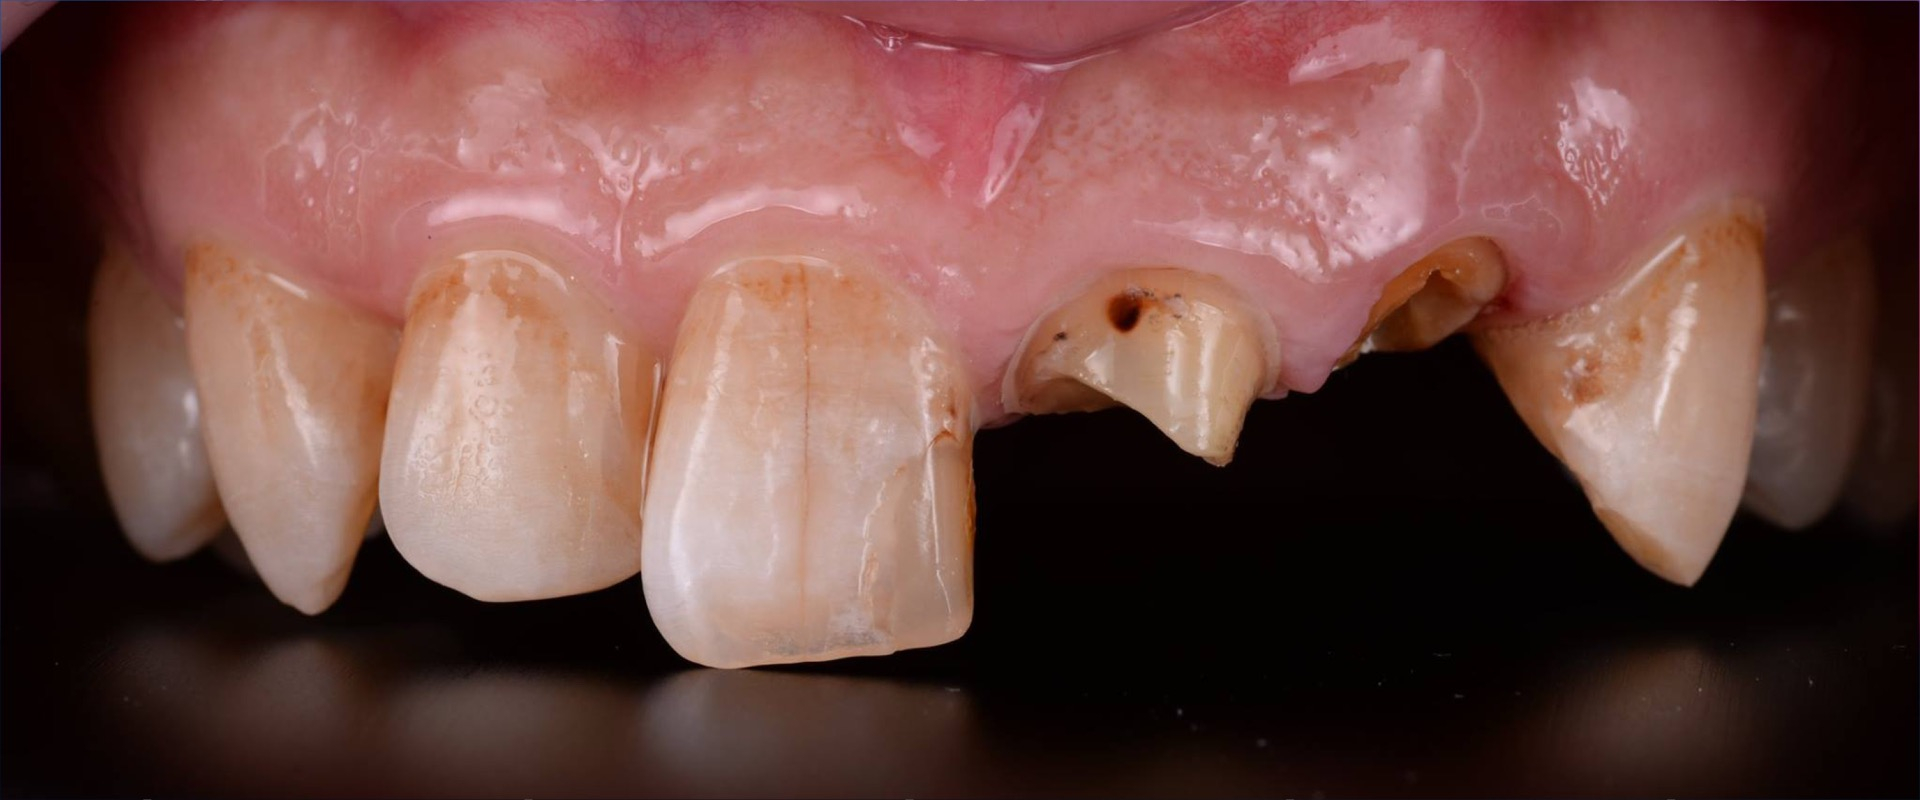

Extrusions-Therapie mit Wurzelstiftversorgung

Erweitere Dein Fachwissen mit unserer Fortbildung zur innovativen Extrusionstherapie, kombiniert mit einer effektiven Wurzelstiftversorgung. Erfahre, wie Du mit einem interdisziplinären Therapieansatz nicht nur Knochen substanzschonend erhalten kannst, sondern gleichzeitig optimale Voraussetzungen für die prothetische Restauration schaffst. Anhand eines detaillierten Patientenfalls, beleuchten wir die essentiellen Schritte von der Revision der Wurzelkanalbehandlung bis hin zur adhäsiven Versorgung mit Wurzelstiften – ohne ästhetische Kompromisse eingehen zu müssen. Tauche tief ein in die Praxis und Theorie einer Behandlungsform, die Zähne erhält und neuen Raum für ästhetische Restaurationen schafft.